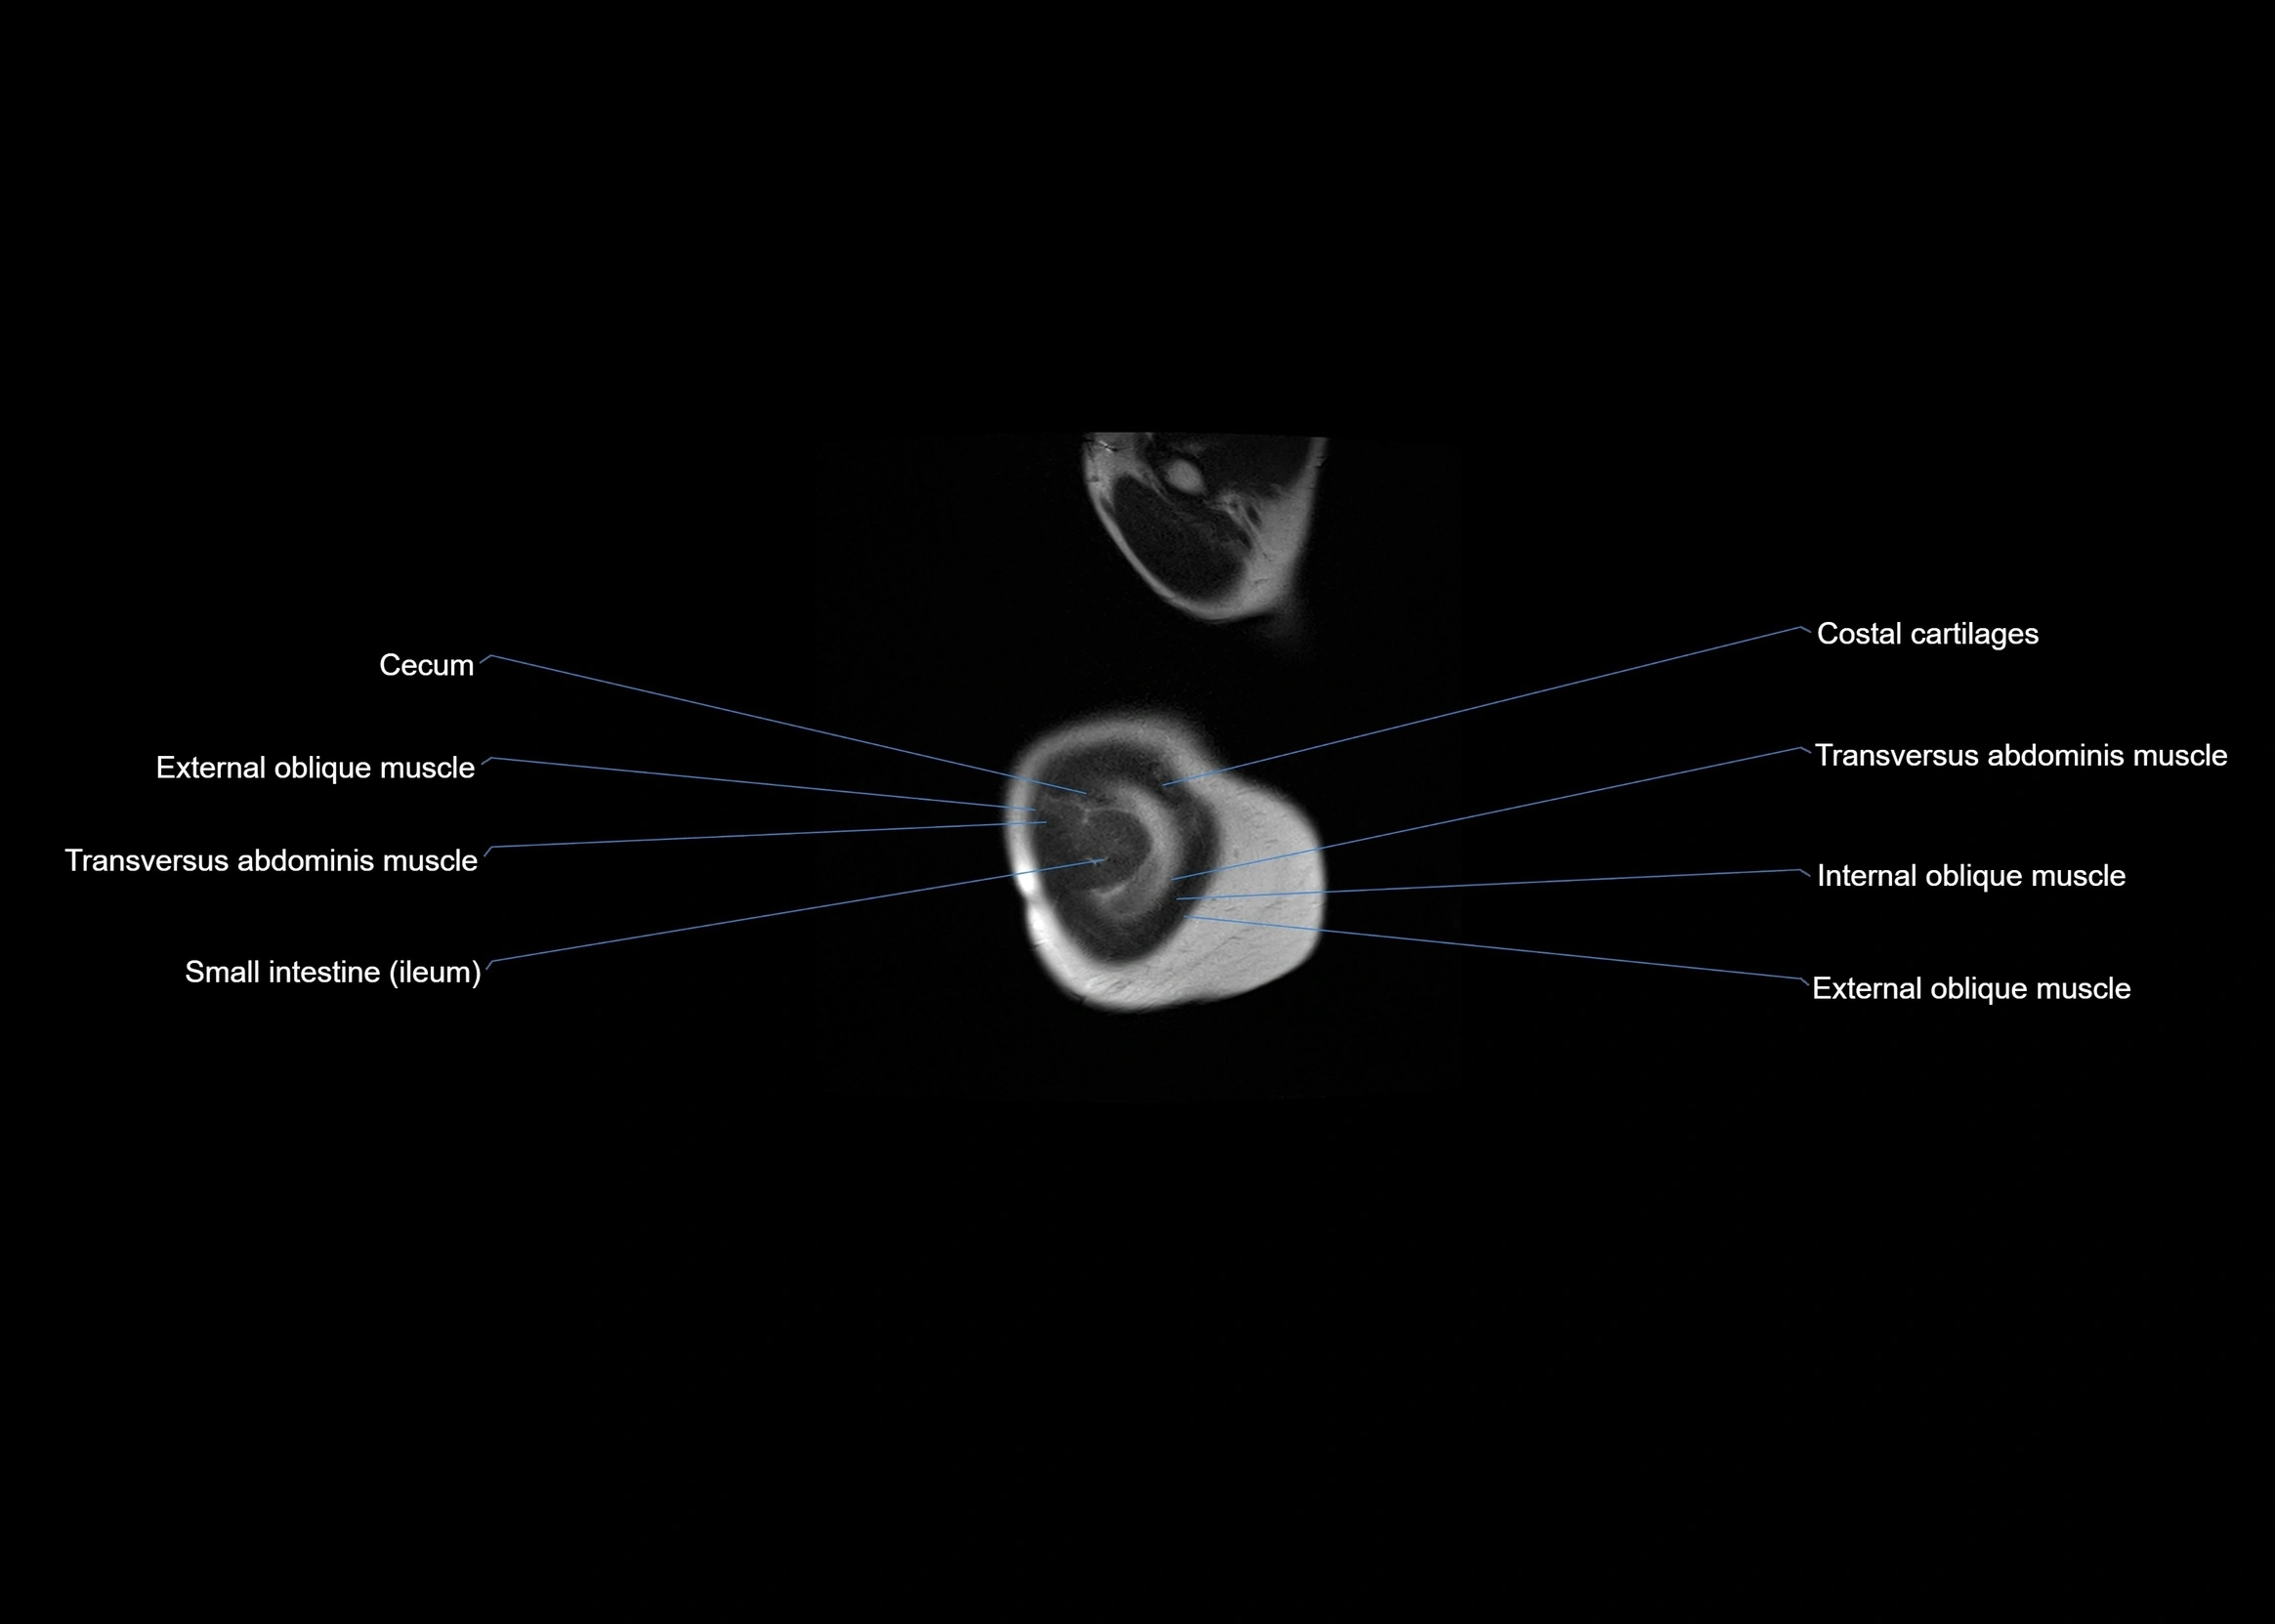

- External oblique muscle

- Transversus abdominis muscle